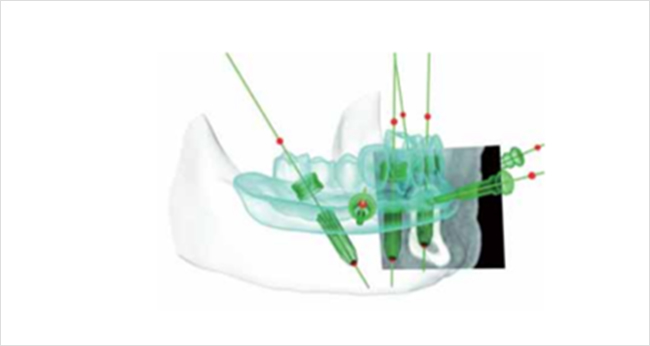

「ノーベルガイド」は、歯肉を切開せずにインプラントを埋入するノーベル独自のガイドシステムです。術前のデジタルシミュレーションとガイドテンプレートで正確な埋入と低侵襲な手術を実現し、患者様のご負担を軽減します。